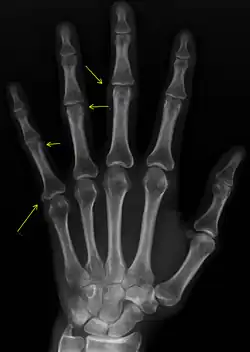

| CREST syndrome (calcinosis and sclerodactyly) | |

CREST causes thickening and tightening of the skin with deposition of calcific nodules ("calcinosis").

Though it is the most easily recognizable manifestation, it is not prominent in all patients. Thickening generally only involves the skin of the fingers distal to the metacarpophalangeal joints in CREST. Early in the course of the disease, the skin may appear edematous and inflamed. Eventually, dermal fibroblasts overproduce extracellular matrix leading to increased tissue collagen deposition in the skin. Collagen cross-linking then causes a progressive skin tightening. Digital ischemic ulcers commonly form on the distal fingers in 30–50% of patients.[3]